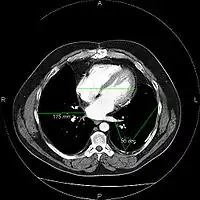

A picture archiving and communication system (PACS) is a medical imaging technology which provides economical storage and convenient access to images from multiple modalities (source machine types).[1] Electronic images and reports are transmitted digitally via PACS; this eliminates the need to manually file, retrieve, or transport film jackets, the folders used to store and protect X-ray film. The universal format for PACS image storage and transfer is DICOM (Digital Imaging and Communications in Medicine). Non-image data, such as scanned documents, may be incorporated using consumer industry standard formats like PDF (Portable Document Format), once encapsulated in DICOM. A PACS consists of four major components: The imaging modalities such as X-ray plain film (PF), computed tomography (CT) and magnetic resonance imaging (MRI), a secured network for the transmission of patient information, workstations for interpreting and reviewing images, and archives for the storage and retrieval of images and reports. Combined with available and emerging web technology, PACS has the ability to deliver timely and efficient access to images, interpretations, and related data. PACS reduces the physical and time barriers associated with traditional film-based image retrieval, distribution, and display.

Most PACS handle images from various medical imaging instruments, including ultrasound (US), magnetic resonance (MR), Nuclear Medicine imaging, positron emission tomography (PET), computed tomography (CT), endoscopy (ES), mammograms (MG), digital radiography (DR), phosphor plate radiography, Visible Light Photography (VL), Histopathology, ophthalmology, etc. Additional types of image formats are always being added. Clinical areas beyond radiology; cardiology, oncology, gastroenterology, and even the laboratory are creating medical images that can be incorporated into PACS. (see DICOM Application areas).